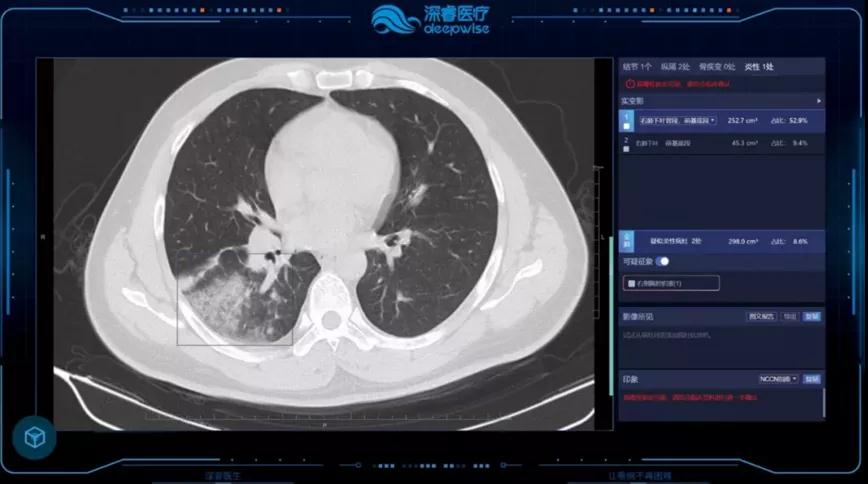

深睿医疗致力于通过突破性的人工智能技术及自主研发的核心算法,为国内外医疗服务机构提供人工智能和互联网医疗解决方案。旗下Dr. Wise® Cloud智能云影像系统可提供精准的人工智能处理建议,让医生可快速高效地在不同场景进行诊断工作,打造多终端远程诊断报告工具。实现区域内中心机构与基层机构的上下联动以及医疗数据的互通互联,为专家、普通医生和患者建立稳定的线上关系,满足各类影像诊断场景。

疫情期间即由Cloudhin云轩搭建硬件系统、深睿医疗推出的全肺AI医学辅助诊断系统发往湖北前线,该系统提供了肺部疾病智能解决方案(新冠肺炎增强版),用于支持抗疫一线医院对于新型冠状病毒肺炎的影像初筛,最终为医生提供符合最新型冠状病毒指南的结构化图文报告,为抗疫一线医务人员的工作提供了强有力的支持。